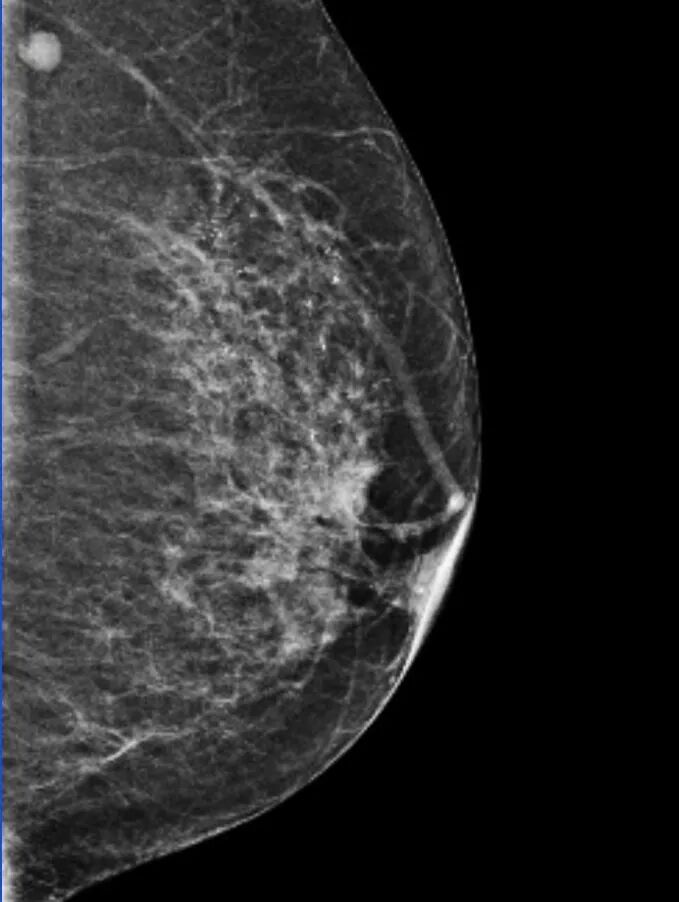

钼靶提示:左乳上部及中央区段样分布细小多形性钙化灶,拟 BI - RADS 4b类,请结合临床,建议活检;

左乳中央区前带局灶性不对称, BI - RADS 0类,建议 MR 检查;

左乳头凹陷。